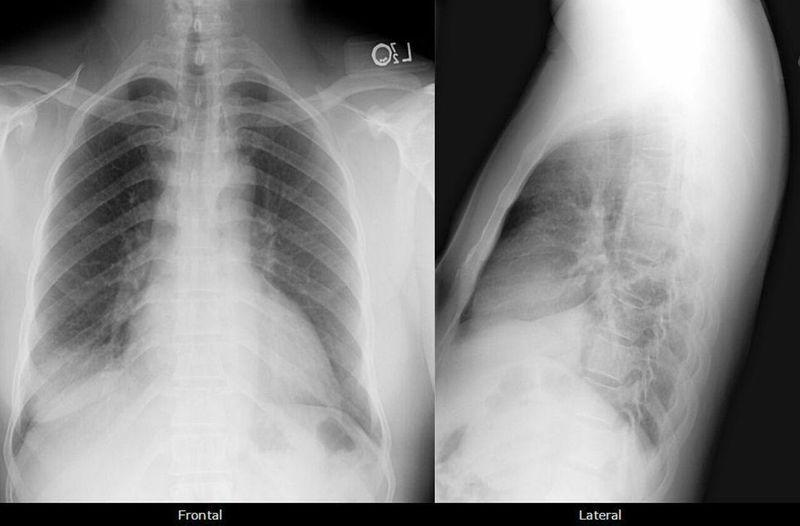

Right lower lobe consolidation, Cardiomegaly

Right lower lobe consolidation, Cardiomegaly Findings: A right lower lobe infiltrate usually silhouettes out the right hemidiaphragm on frontal and/or lateral views. A positive lateral spine sign (density to lower thoracic spine) is also usually evident.